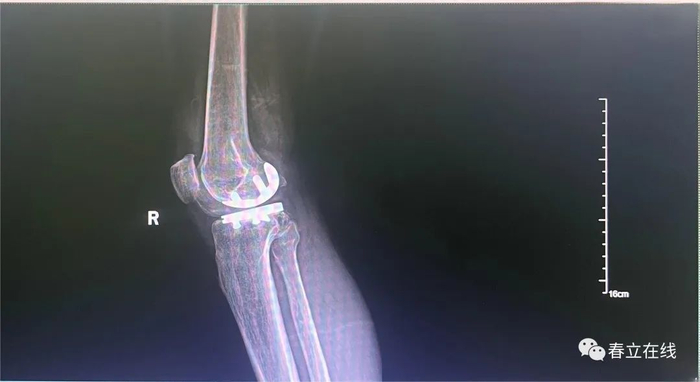

// 术后片

病例二